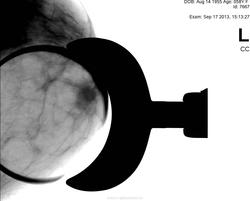

Да, есть опухоль.. но пока небольшая

Слева опухолью Справа сгрукированые кальцинаты BIRADS 4 с двух сторон